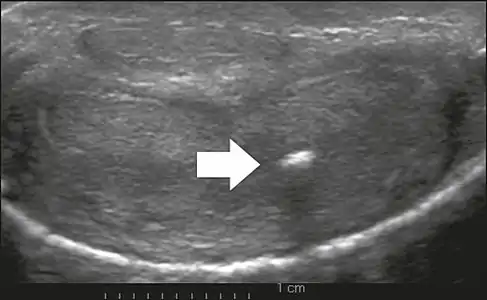

On penile ultrasonography, the typical appearance is hyperechoic focal thickening of the tunica albuginea. Due to associated calcifications, the imaging of patients with Peyronie's disease shows acoustic shadowing, as illustrated in figures below. Less common findings, attributed to earlier stages of the disease (still mild fibrosis), are hypoechoic lesions with focal thickening of the paracavernous tissues, echoic focal thickening of the tunica without posterior acoustic shadowing, retractile isoechoic lesions with posterior attenuation of the beam, and focal loss of the continuity of the tunica albuginea.

In the Doppler study, increased flow around the plaques can suggest inflammatory activity and the absence of flow can suggest disease stability. Ultrasound is useful for the identification of lesions and to determine their relationship with the neurovascular bundle. Individuals with Peyronie's disease can present with erectile dysfunction, often related to venous leakage, due to insufficient drainage at the site of the plaque. Although plaques are more common on the dorsum of the penis, they can also be seen on the ventral face, lateral face, or septum.[13]

Transverse ultrasound of the penis, in a ventral view, in the middle portion of the penis. Note the echoic image with posterior acoustic shadowing, corresponding to calcification (arrow), in the left corpus cavernosum.[13]